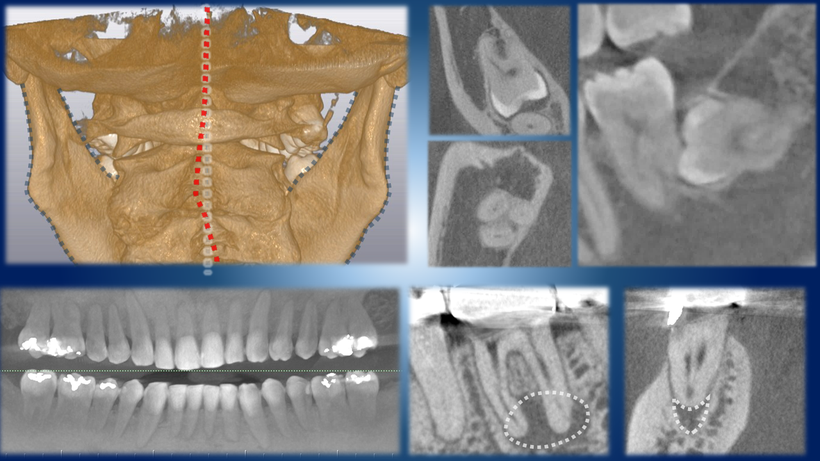

頸椎と顎の3次元的な位置確認、根の方向確認(左上、左下、160cmモード)

埋伏智歯の位置(右上)、根の病巣と根の3次元的形態確認(右下)(詳細モード)

CTスキャンで得られる情報、顎の3次元像(左上)、埋伏歯と神経の関係(右上)、全体の歯の状態確認(左下)、根の状態詳細の確認(右下)

左上の像では頸椎と顎が歪んでいるのが分かります。

右上の画像で親知らずと下歯槽神経の位置関係が確認できます。

左下のパノラマモードで

右下では様々な角度から歯の根の形状を確認できます。